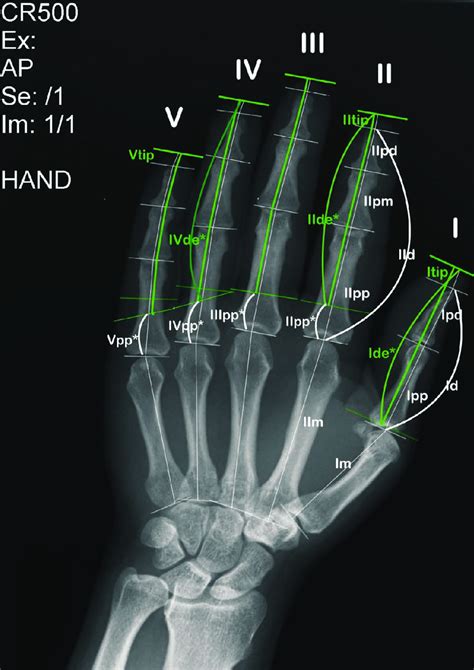

So, why would your doctor order a finger X-ray ? The reasons can be varied, but the common thread is that they’re trying to get a good look at the bones and tissues in your fingers. Think of it like this: if you’re experiencing pain, swelling, or have an injury to your hand or finger, an X-ray can help your doctor see what’s going on beneath the skin. Let’s break down some of the most common reasons you might need a finger X-ray.

First off, fractures . This is probably the most frequent reason. If you’ve taken a tumble, slammed your finger in a door, or experienced any kind of trauma to your hand, there’s a good chance your doctor will want to check for broken bones. X-rays are excellent at showing these breaks, helping doctors determine the severity and the best course of treatment. The X-ray can reveal the location, type (e.g., simple, comminuted), and displacement of the fracture, which is super important for deciding if you need a cast, surgery, or just some good old-fashioned rest.

Next up, we have dislocations . A dislocated finger means the bones have moved out of their normal position at a joint. X-rays are crucial here because they allow doctors to visualize the misalignment and confirm the diagnosis. They can also make sure there aren’t any associated fractures, which could complicate things. If you’ve got a dislocated finger, an X-ray is your first step to getting it back in place properly.

Then there’s the ever-present problem of arthritis . Over time, the joints in your fingers can wear down, leading to pain and stiffness. X-rays can show the changes associated with arthritis, such as narrowing of the joint space, bone spurs, and other telltale signs. This helps doctors diagnose the specific type of arthritis and develop a plan to manage your symptoms. If you’ve been experiencing chronic finger pain, an X-ray might be part of the puzzle.